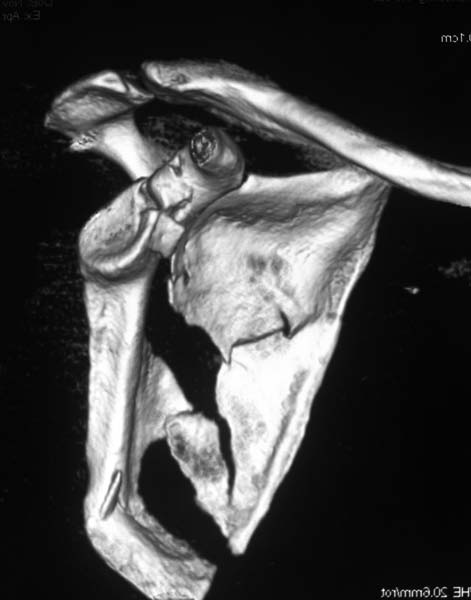

КТ отправляю

Я бы оставил все как есть. ориентация гленоида нормальная, перелом суставной поверхности без существенного смещения

Латеральный край лопатки развернут в антеверсию вместе с суставной впадиной лопатки, плюс суставная впадина при этом мигрировала медиально. В таком случае считаю важным развернуть латеральную "колонну" обратно путем остеосинтеза тела лопатки. Внутрисуставные фрагменты пока загадка. Сами по себе они могут особо не мешать, но там может быть тяжелый SLAP.